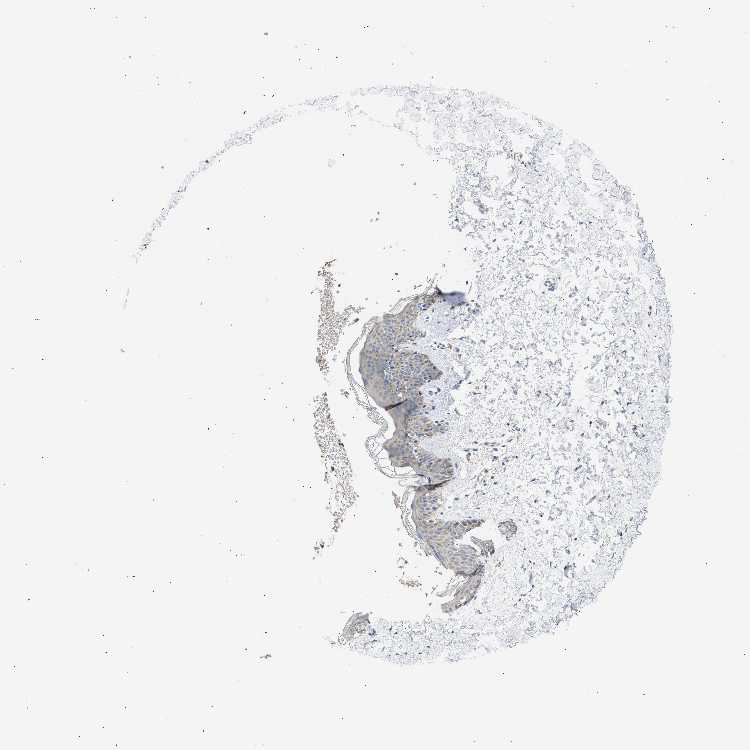

SKIN 1 - Antibody stainingi

Antibody staining in the annotated cell types in the current human tissue is reported as not detected, low, medium, or high, based on conventional immunohistochemistry profiling in selected tissues. This score is based on the combination of the staining intensity and fraction of stained cells.

Each image is clickable and will lead to virtual microscopy that enables deeper exploration of all samples and also displays staining intensity scores, fraction scores and subcellular localization as well as patient and tissue information for each sample.

Antibody HPA004801

Langerhans Medium

Fibroblasts Not detected

Keratinocytes Medium